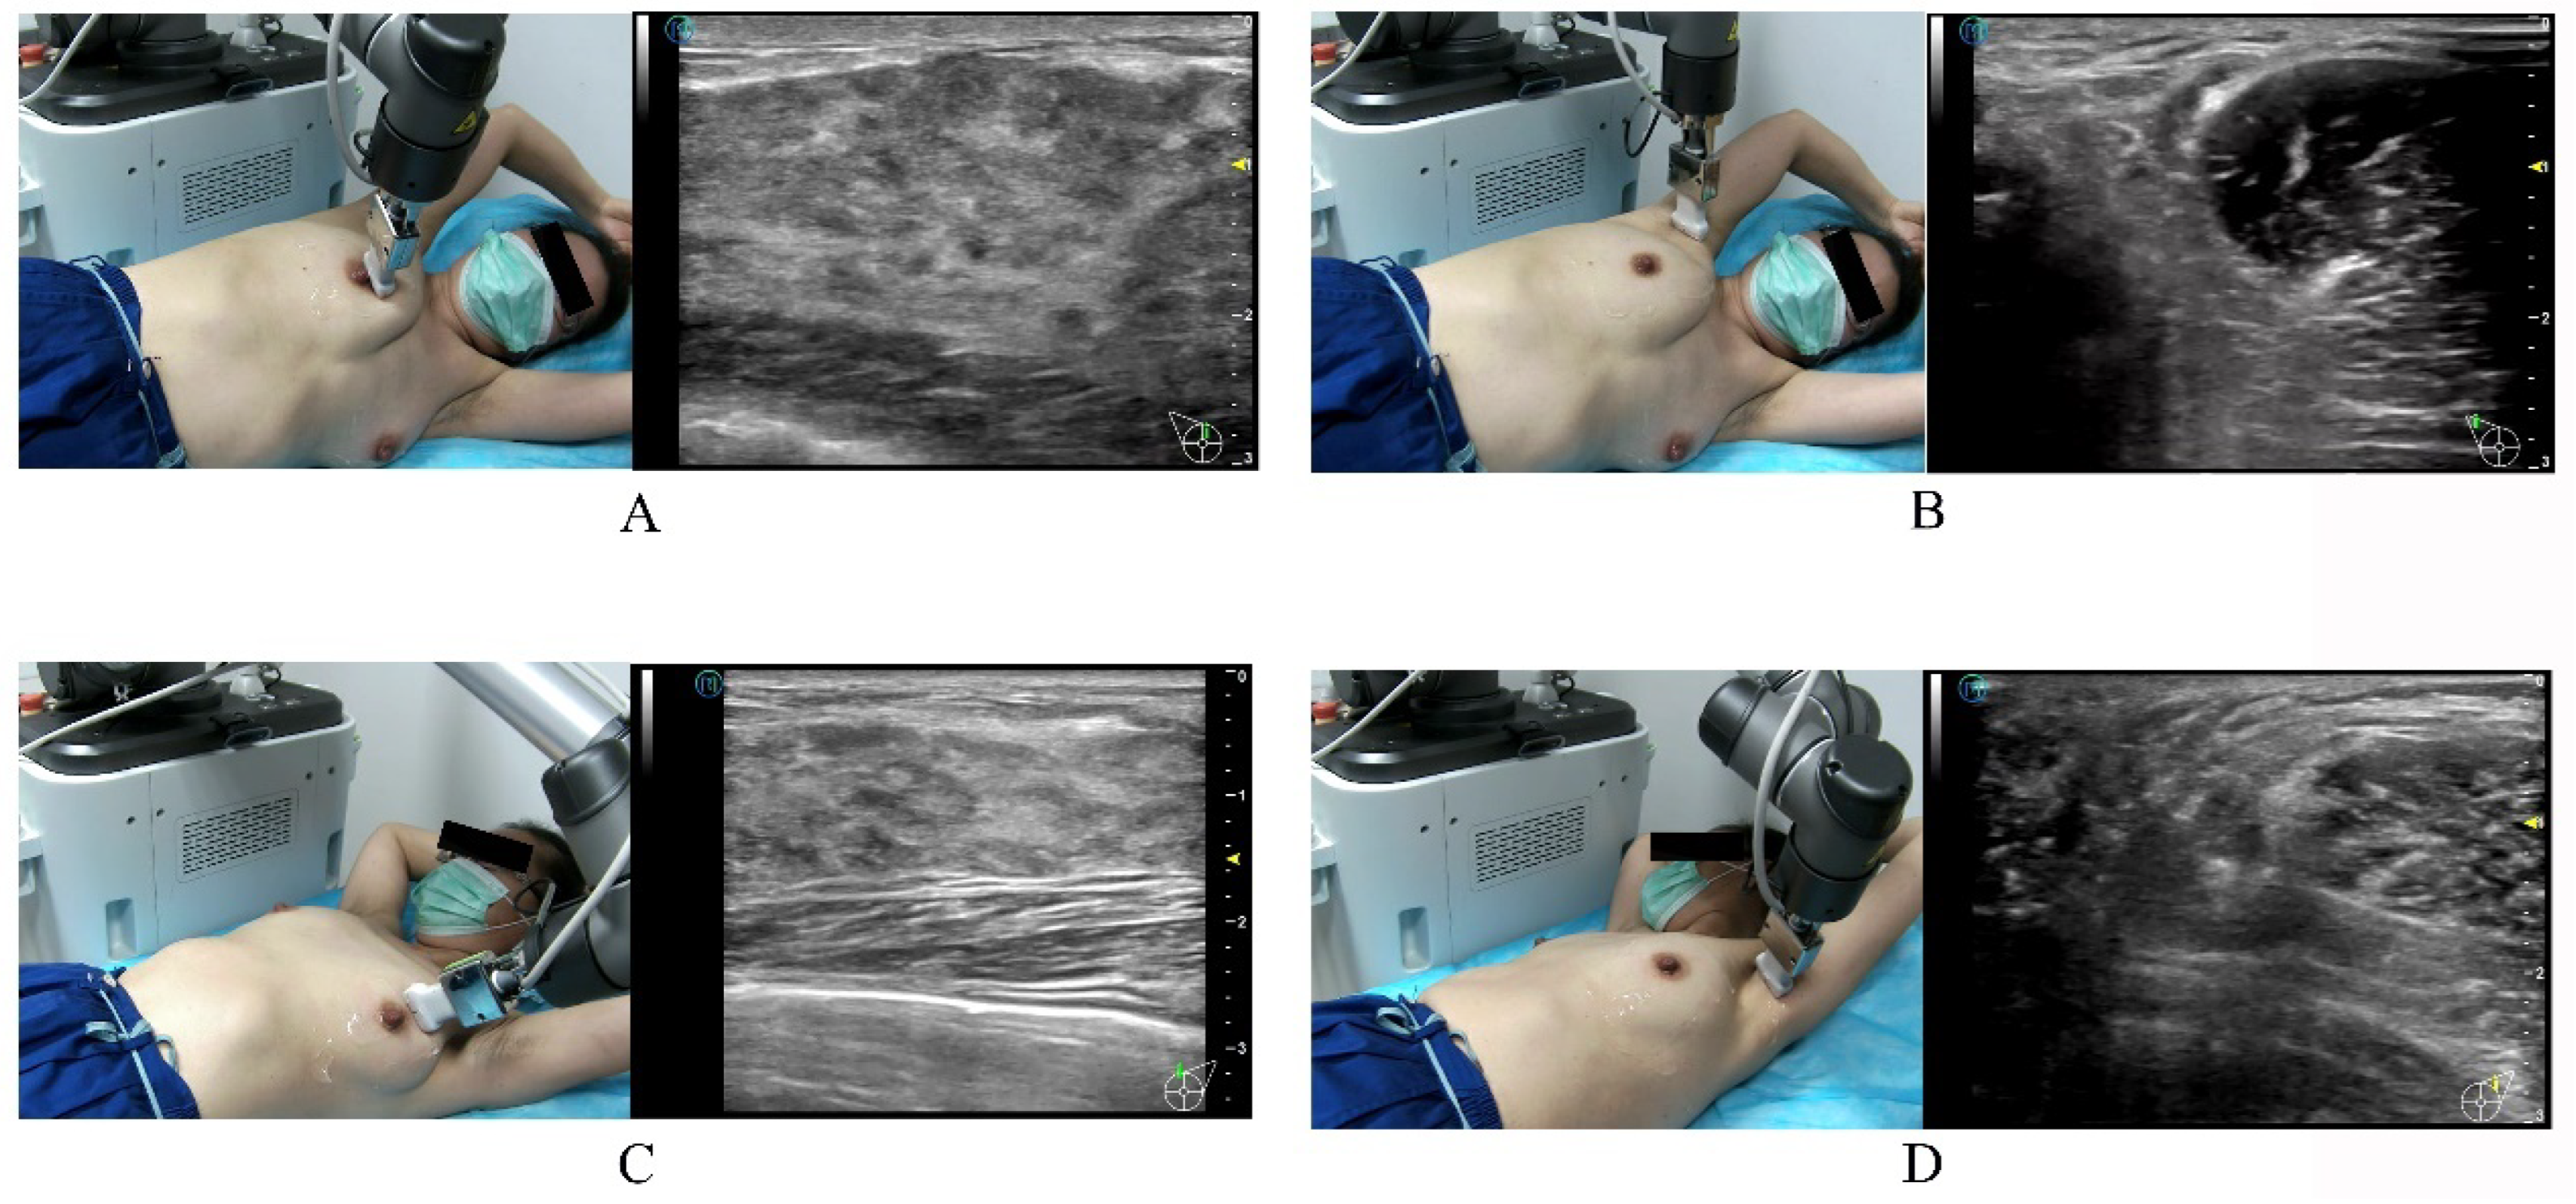

Figure 1.

Illustration of the doctor-side subsystem and patient-side subsystem of the 5G-based telerobotic ultrasound system in two different scenarios. (A) The tele-sonologist at Shanghai Tenth People’s Hospital manipulates a dummy US probe to perform 5G-based telerobotic breast US examinations remotely for (B) the patients in Chongming Second People’s Hospital of Chongming Island and (C) the patients in a mobile car located in Anji County. (D) An on-site sonologist performs conventional breast US examination for the patients in Chongming Second People’s Hospital. (US, ultrasound; 5G, fifth generation).

The doctor-side subsystem of Shanghai Tenth People’s Hospital in central Shanghai was equipped with a robot control console, US imaging control system, and audio–video communication system (Figure 1). The robot control console consisted of a mobile dummy US probe (built-in gesture sensor and “UP” button) and a contact plate (built-in position and pressure sensors). By associating the robot coordinate system with the robot control console coordinate system and motion transformations, the robot control console could manage six DOFs of the robotic arm to achieve the desired movement of the probe. Thus, the action of the operator was consistent with the action of the robotic arm. The gesture sensor managed three DOFs for rotation, the position sensor managed two DOFs for the movement on the horizontal plane, and the pressure sensor and “UP” button managed one DOF for the down and up movements, respectively. Using the US system control panel on the doctor’s side, all parameters and functions of the US imaging system, including gain, depth, focus, measurement, and colour Doppler parameters on the patient’s side subsystem, could be adjusted and implemented in real-time by the tele-sonologist. During the telerobotic US examination, the quantified transmission delay was measured and dynamically displayed on the screen to the remote doctor. The colour of the icon was green when the delay time was less than 100 ms, yellow when it was 100–500 ms, and red when it was greater than 500 ms. It could assist the tele-sonologist in determining the delay status.

The same patient-side subsystems were located in Chongming Second People’s Hospital of Chongming Island and in a mobile car parked in Anji County (Figure 1). The patient-side subsystem was equipped with a six-DOFs collaborative robotic arm (UR5; Universal Robots, Odense, Denmark), a portable US imaging system with a 5–12 MHz linear array transducer (Wisonic Clover 60; Huasheng Medical Systems, Shenzhen, China), and an audio–video communication system. The 6-DOF robotic arm could conduct six-dimensional motion in space to control the posture of the US transducer. The positioning accuracy was up to 0.1 mm. A force sensor at the front-end robotic arm provided real-time force feedback information. During the interaction between the US transducer and the human body, the force sensor recorded three-dimensional (3D) force information in real time. The vertical component of the 3D force was fed back to the controller as the actual contact force. Additionally, the sensitivity of the contact force could be accurate to 0.1 N. Meanwhile, the magnitude of the contact force was displayed synchronously and dynamically on the screen of the doctor-side subsystem to the tele-sonologist. Screen imaging of the US machine and scene, including the motion of the robotic arm, position of the US transducer, and posture of the patient, shot by an angle-adjustable camera with the function of amplification, could be transmitted to experts in real time and dynamically displayed using the doctor-side subsystem to the tele-sonologist.

The tele-sonologist instructed the patient to assume the appropriate breast examination posture with the help of the on-site assistant via the audio–video communication system. The on-site assistant applied adequate coupling agents to the bilateral breasts and axillae of the patient. The tele-sonologist activated the examination button, and the robot arm was moved over the patient. The on-site assistant then dragged the US transducer and positioned it on the patient’s breast (quick positioning). By manipulating the dummy probe, the tele-sonologist then scanned the four quadrants of the breast and the nipple and axilla (Figure 2).

Illustration of the positions of the patient for 5G-based telerobotic breast ultrasound examination. When scanning the right breast (A) and axilla (B), the patient is placed in the left lateral position with the arms raised overhead. When scanning the left breast (C), the patient is placed in the supine position with the arms raised overhead. While scanning the left axilla (D), the patient is in the right lateral position with the arms raised overhead.